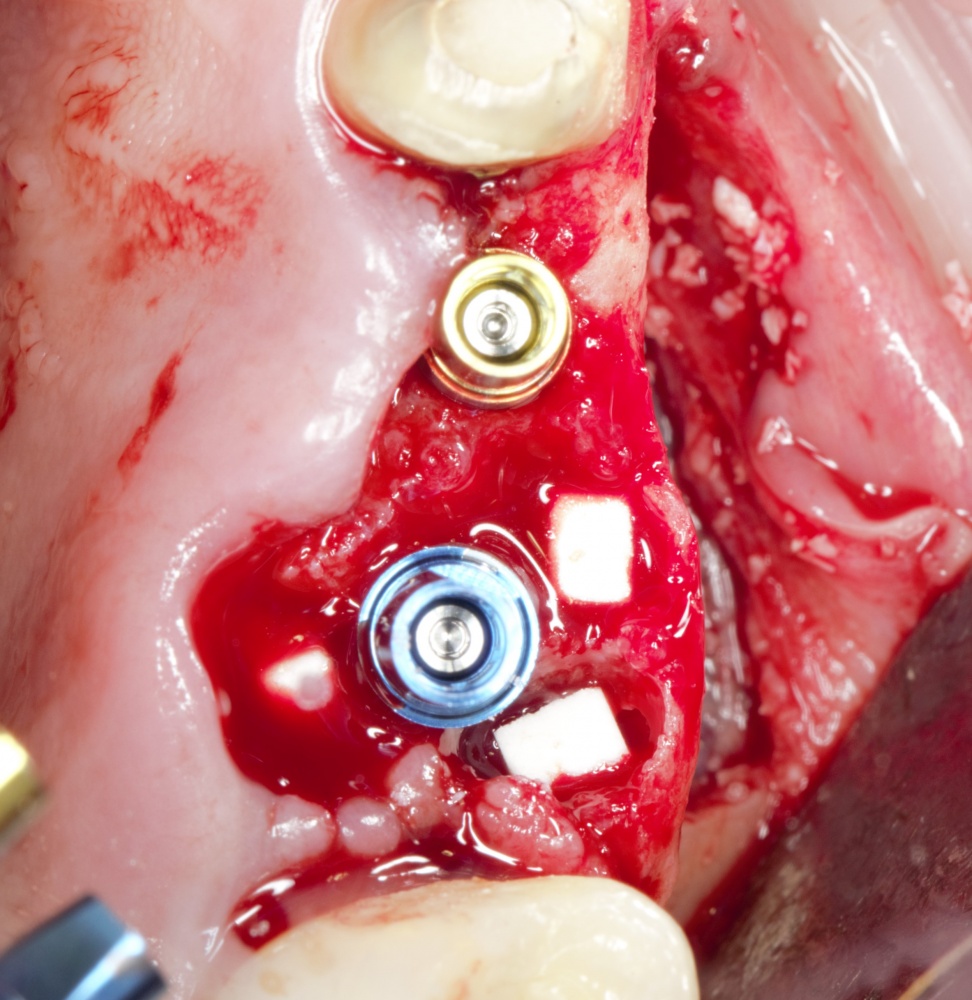

Я зафиксировал костный блок практически без адаптации на несколько винтов. Обрати внимание, что винты находятся в зоне, где не планируется установка имплантатов. Фиксация должна быть надежной, поскольку мне еще предстояла подготовка лунок для имплантатов. Трех винтов для этого вполне достаточно.

Дальнейшая адаптация костного блока свелась к сглаживанию острых краев. После чего я приступил к подготовке лунок и установке имплантатов.

Установка имплантатов.

Напомню, что для этой работы я выбрал субкрестальные имплантаты Ankylos C/X. Они прекрасно сочетаются с любым методом остеопластики.

Я не планирую установку супраструктур или коронок, поэтому на уровень первичной стабильности можно положить болт. Даже наоборот — чем меньше крутящий момент при установке, тем лучше. Для имплантатов Ankylos и подобных им, это особенно важно. В общем, момент силы при установке — не более 10-15 Нсм.

Глянем на то, что получилось: